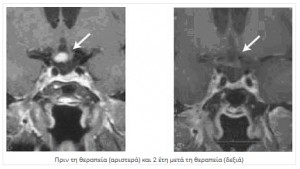

Γενικά όμως για τα καλοήθη , βαθμού Ι, που είναι ασυμπτωματικά προτείνεται η χειρουργική εξαίρεση ή η ακτινοχειρουργική. Σε μηνιγγιώματα υψηλότερου βαθμού (ΙΙ/ΙΙΙ) προτείνεται συνδυασμός και των δυο θεραπειών, χειρουργείου και ακτινοθεραπείας.

Για τα μηνιγγιώματα που δεν είναι εφικτή η πλήρης χειρουργική εξαίρεση, η ακτινοχειρουργική συμπληρώνει τον θεραπευτικό αλγόριθμο.

Υπάρχουν και μηνιγγιώματα που αντιμετωπίζονται αποκλειστικά με ακτινοχειρουργική λογω της θέσης τους: σηραγγώδους κόλπου, οβελιαίο κόλπου, οπτικού νεύρου και σε αυτά που αναπτύσσονται όπισθεν του αποκρίματος